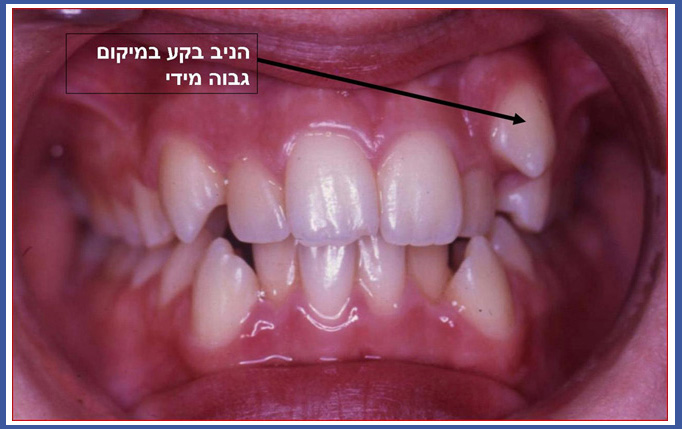

יש מצבים בהם שן לא מצליחה לבקוע למקומה בקשת השיניים ונשארת כלואה בחניכיים.

1. כליאה עקב צפיפות בקשת השיניים: המקום לבקיעת השן הצטמצם ואין לה מקום לבקוע. במקרה כזה השן תבקע לעמדה לא נכונה או שתישאר כלואה בחניכיים.

3. טעות במסלול הבקיעה: שן קבועה מתחילה את התפתחותה בעומק החניכיים ועם הזמן מתחילה לבקוע.שיניים שלהן מסלול בקיעה ארוך עלולות "לטעות" וכתוצאה יישארו כלואות בחניכיים במיקום לא נכון. מצב כזה אופייני בעיקר לניבים עליונים להם מסלול בקיעה ארוך מאד (כליאה כזו קיימת גם בשיניים אחרות בשכיחות נמוכה יותר). שכיחות כליאה של ניב עליון באוכלוסיה 1%-3%.